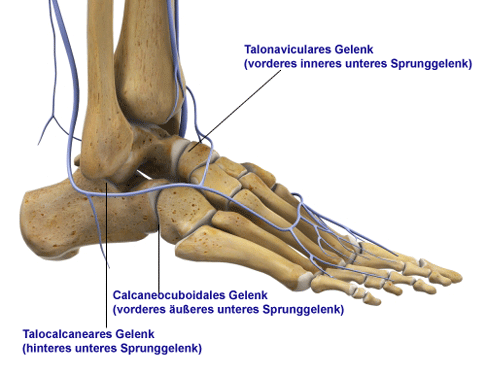

Aufbau des unteren Sprunggelenks

Es werden zwei Sprunggelenke unterschieden:

- Oberes Sprunggelenk (kurz OSG) zwischen Sprungbein und Schienbein bzw. Wadenbein

- Unteres Sprunggelenk (kurz USG) gebildet aus Sprungbein, Fersenbein, Kahnbein und Würfelbein

Wie ist das untere Sprunggelenk aufgebaut und welche Funktion hat es?

Das untere Sprunggelenk ist deutlich komplexer aufgebaut als das obere Sprunggelenk. In diesem mehrteiligen Fußgelenk stehen Sprungbein (Talus), Fersenbein (Calcaneus) sowie Würfelbein (Os cuboideum) und Kahnbein (Os naviculare) in Kontakt. Sie regulieren die Stellung des Fersenbeines und Rückfußes nach Innen oder Außen bei unebenem Untergrund.